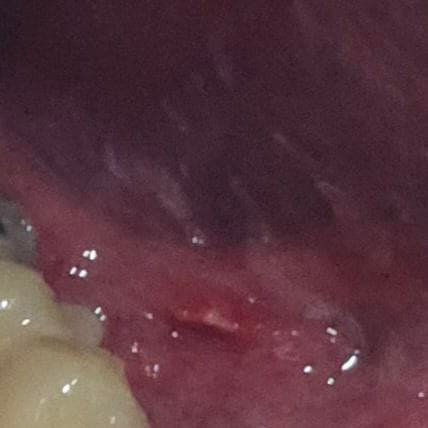

사진 첨부합니다. 혀 밑에 염증이 생겼는데 염증이 생기는 원인과 지금 생긴 염증의 이름이 있다면 알려주세요. 자연치료에는 얼마나 걸릴지도 여쭤봅니다

사진으로는 정확한 진단 불가능하며 병원 방문하셔서 직접 육안으로 진료 보셔야 합니다특히 올려주신 사진은 너무 어두워서 병변이 잘 안보여요. 확인 불가입니다

우선 말로 말씀하신 부분 관련 답변 드리자면 혀 밑에 생긴 염증은 보통 설하염(혀 밑 염증) 또는 구강 점막염의 일종일 가능성이 있습니다. 원인은 다양할 수 있는데, 대표적으로는 구강 위생 불량, 바이러스(특히 헤르페스), 세균 감염, 기계적 자극(예: 이물질, 잘못된 칫솔질), 영양결핍(특히 비타민 B군 부족), 스트레스 등이 있습니다.

때로는 치아나 틀니 문제, 혹은 알레르기 반응으로도 염증이 생길 수 있구요. 만약 염증 부위가 붓거나, 고름이 차거나, 통증이 심하면 세균성 감염이 진행된 것일 수도 있어요

자연치료는 염증의 원인과 심한 정도에 따라 다르지만, 가벼운 경우라면 보통 1주일 내외로 저절로 호전됩니다. 이 기간 동안은 구강을 청결히 하고, 자극적인 음식(매운 것, 뜨거운 것, 딱딱한 것)을 피하는 것이 중요합니다. 염증이 2주 이상 지속되거나 통증이 심해지면 반드시 병원을 방문하여 진료를 받아야 합니다